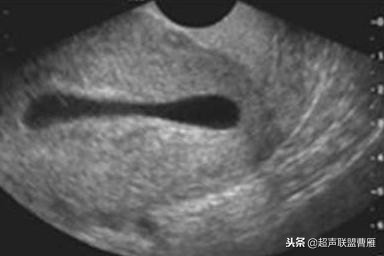

有的图像卵黄囊YS只是两条平行的细短线

妊娠37天出现卵黄囊

在妊娠妊娠38天前后(36-40)天可以见到卵黄囊。 孕囊在6-9mm的可以见到其中有卵黄囊。